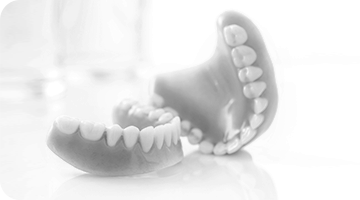

틀니와 임플란트는 이렇게 다릅니다.

틀니 임플란트

씹을 때 잇몸살이 눌려 아프고,

틀니가 입천장 전체를 덮어 음식을 먹을 때 구역감이 큰 편

통증 / 구역감 진짜 내 치아처럼 심겨지기에

통증, 구역감 모두 없음

밥먹을 때 자꾸 빠져서 사용이 불편함 고정력 / 사용감 잇몸뼈에 심어 고정된 형태로 빠질일 없음

평균 5~10년 수명 관리에 따라 반영구적 사용

(최소 10년 이상)